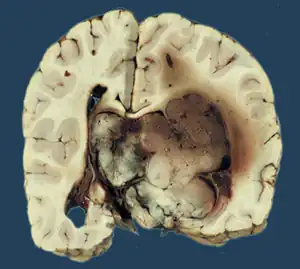

Micrograph of a choroid plexus papilloma. H&E stain. -

Plexuspapillom Detail -

Plexuspapillom Overview